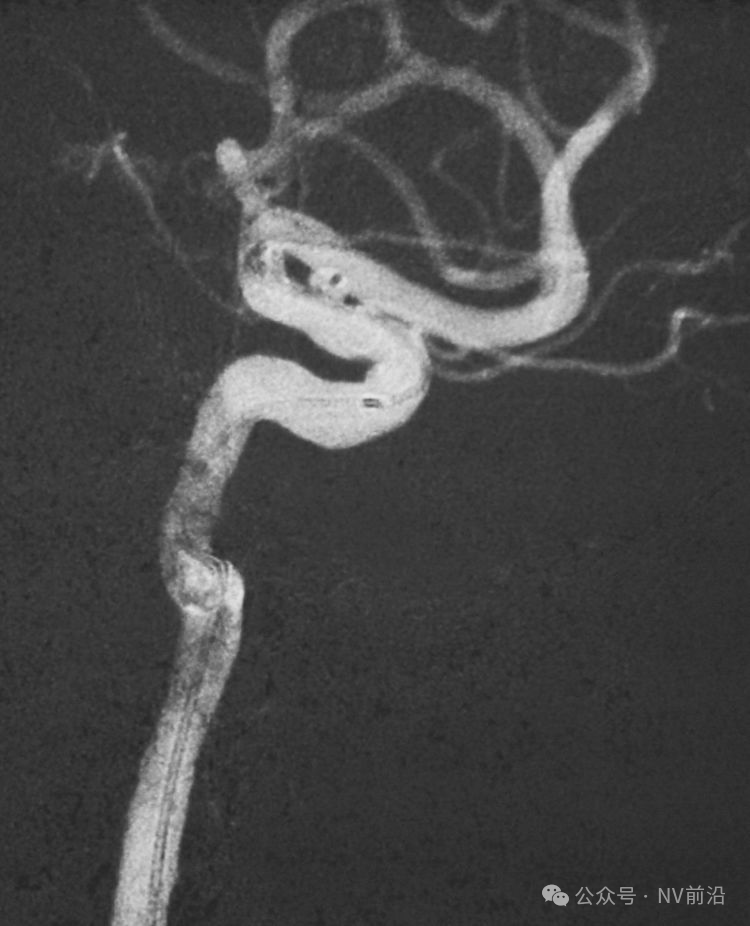

工作位造影

Traxcess 14微导丝可以进入瘤腔,但头端塑成S形的Echelon 10微导管无法跟入。

将微导管在虹吸弯处成襻,越过瘤颈,管头折返钩入瘤腔,即所谓回马枪技术。